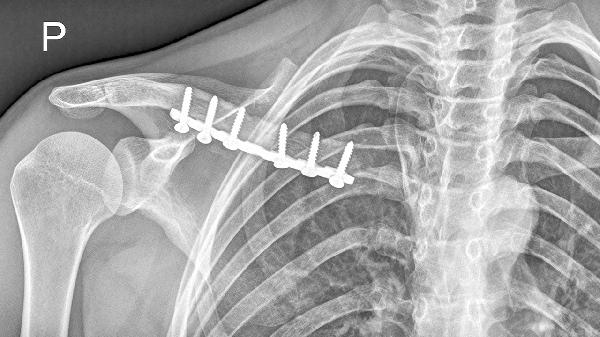

4、胸锁关节紊乱

该关节半脱位或劳损会导致锁骨内侧端压痛,常见于单侧提重物或外伤后。关节活动时有弹响感,X线检查可明确诊断。急性期需固定制动,配合洛索洛芬钠片消炎镇痛,慢性期可通过关节松动术改善功能。康复阶段应加强胸小肌拉伸训练。